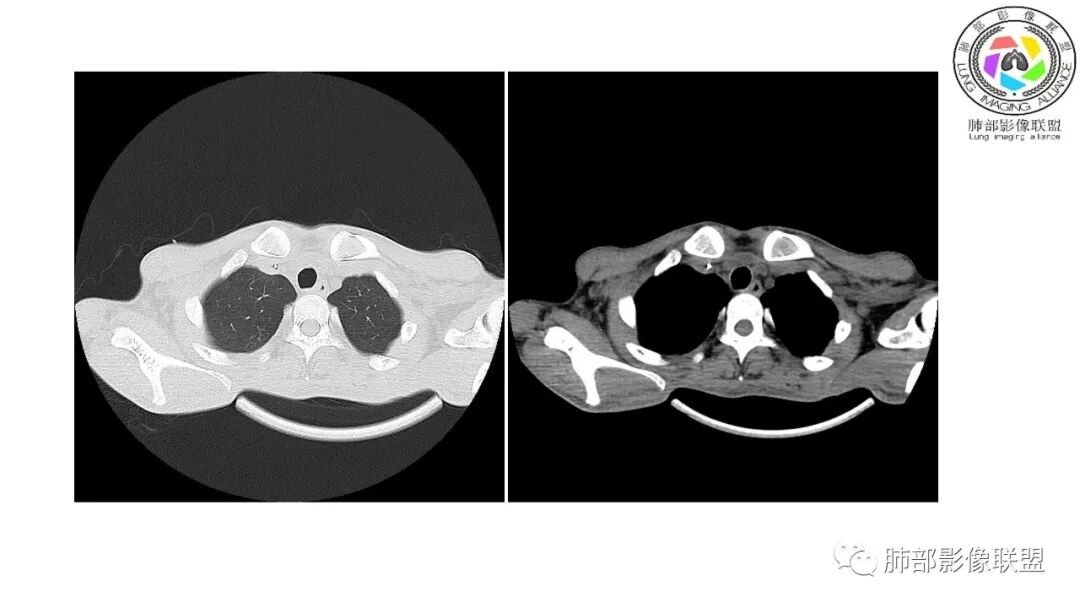

影像与临床:1.青年男性,HlV阳性,颜面部皮疹(未提供皮疹图像)、发热(高热),实验室CRP、PCT高,T-Spot阴性。2.右肺下叶空洞结节,壁厚不均,边界清楚,其内线状影,未见液平及钙化,未见卫星灶,纵隔淋巴结增大,双侧腋窝见增大淋巴结。心腔内低密度提示贫血可能。肝脾影增大,未见结节影及块影。腹膜后见多发增大淋巴结。

综合分析:本例肺部影像学改变并不具有特征性,空洞性病灶须与多种疾病鉴别,但年轻HIV阳性患者,高热,皮疹,肝脾增大,纵隔、腋窝、腹膜后见多发增大淋巴结等都强烈提示马尔尼菲篮状菌感染的可能性。